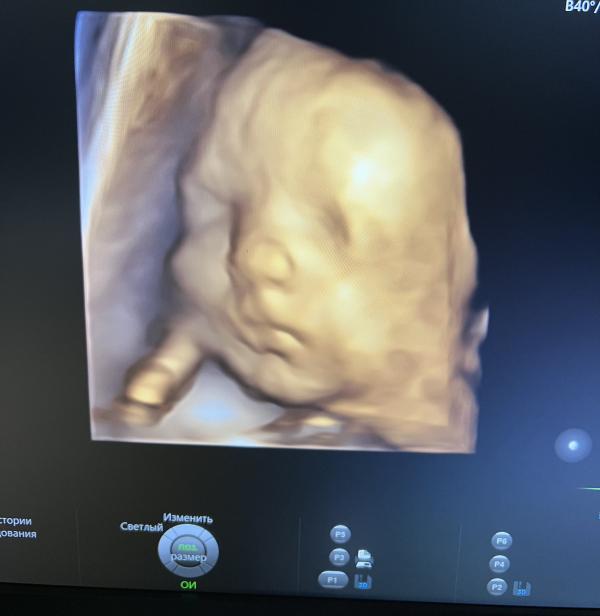

3й скрининг позади, бесплатное 3Д фото в ЖК! Малышка крупненькая - декрет близко?

Время быстро летит, уже и 3й скрининг за плечами. Даже сделали 3Д фото, бесплатно в обычно ЖК, шоооок, я и не просила…

Сказали малышка крупненькая)

1,8 кг)